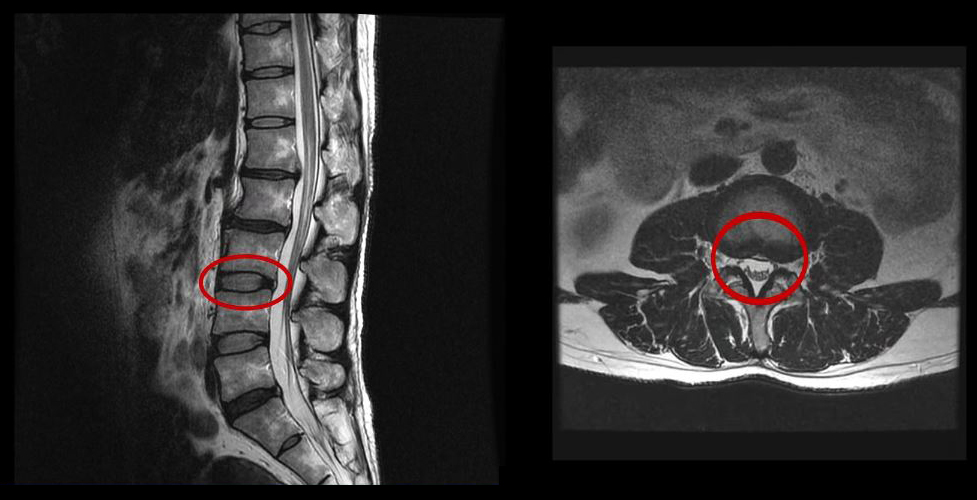

그런데 이 환자분의 MRI를 보면 여러 마디에 퇴행성디스크가 있습니다.

이 환자분은 MRI상으로 거의 대부분 마디의 디스크가 퇴행되고 수핵이 밀려나와 있으며, 정상적인 허리 마디는 4-5번 하나 정도입니다. 그렇기 때문에 MRI만 보면 아마 대부분의 병원에서 허리디스크탈출 또는 퇴행성디스크로 인한 허리통증 및 다리통증으로 진단하고 치료할 것입니다. 이분도 그래서 20년간 그런 치료를 무수히 많이 받았으나 그 어떤 치료도 별 도움이 되지 않았습니다.

이 환자분처럼 오랜 기간 만성적인 허리통증이 있고, 엉덩이가 저리면서 심지어는 양쪽 다리저림까지 있는 환자분들이 많습니다. 그런데 이 환자분의 MRI를 보면 여러 마디의 퇴행성디스크, 디스크탈출, 황색인대의 두꺼워짐, 후관절의 퇴행 등 다양한 병변들을 가지고 있는 걸 볼 수 있는데요. 그렇기 때문에 많은 병원에서 이분을 디스크로 진단하고 거기에 따른 치료가 이루어졌습니다. 그러나 저희가 보기에는 이분의 MRI상으로 보이는 여러 마디의 디스크 문제가 이 환자분이 갖고 있는 증상을 설명할 수 없었습니다.

만성적인 허리통증은 그 원인을 찾기가 매우 힘듭니다. 왜냐하면 만성 허리통증의 대부분은 근육의 기능 문제가 원인인데, 근육의 기능 문제는 MRI상으로는 보이지 않기 때문입니다. 또 양쪽 다리가 저린 이유도 MRI만으로는 알 수 없습니다.

그래서 저희는 이 환자분의 문제를 근육 문제로 보고, 4주간의 입원재활치료를 시행하였습니다. 입원치료 기간 내내 거의 모든 활동량을 최소한으로 줄이고, 근육을 초기 상태로 리셋하여 재활하는 치료를 진행한 것입니다.